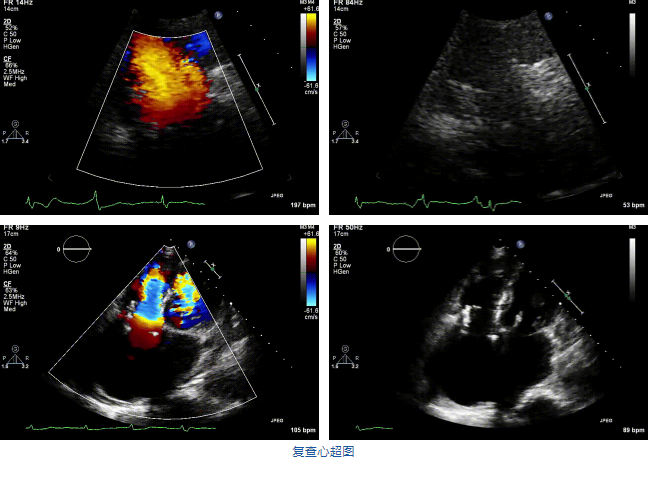

2021年12月7日,復旦大學附屬中山醫院葛均波院士團隊完成的首批兩例LuX-Valve Plus經血管三尖瓣置換患者順利出院,從患者入院至出院僅歷時一周時間,出院時患者狀態恢復良好,復查心超三尖瓣無反流。

結合術前CT評估結果,葛均波院士團隊最終決定選用LuX-Valve Plus 50mm和55mm兩種型號的瓣膜,并于2021年11月30日順利完成LuX-Valve Plus經血管三尖瓣置換術,手術室即刻拔除氣管插管,術后第二天轉出心內科監護室,下床活動。術后患者三尖瓣反流癥狀得到顯著改善,復查心超結果顯示人工三尖瓣瓣膜支架固定穩定,瓣葉關閉形態未見異常,未見明顯反流。